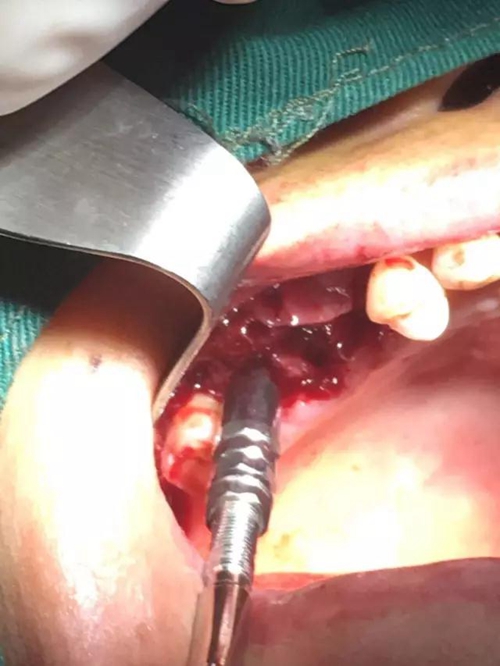

【病例分享】內(nèi)提,用自體骨柱,不用骨粉

2.jpg